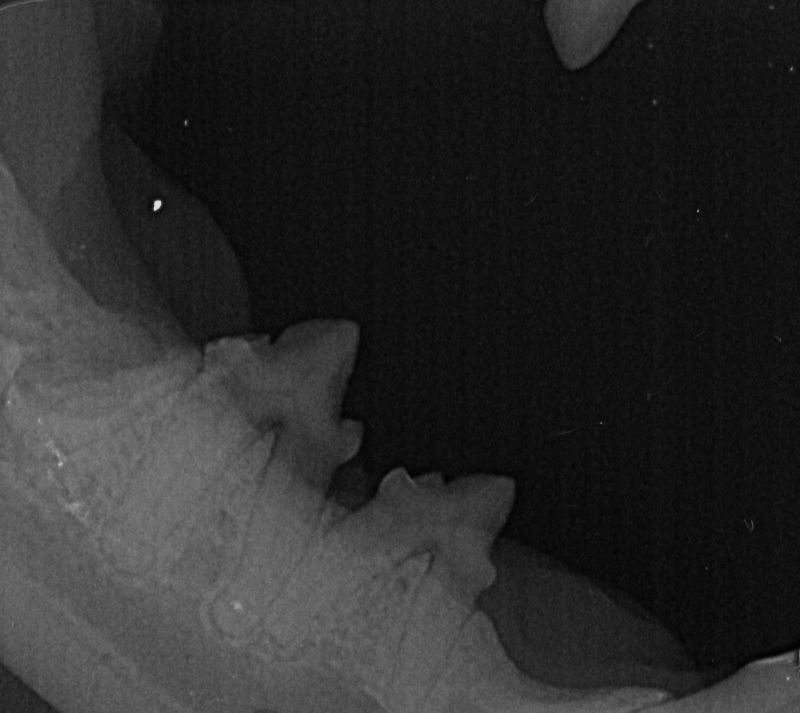

We like to avoid removing teeth where possible, and have a state of the art dental xray so we can check the health of the teeth below the line. This provides us with more information than just the visual appearance, giving us more opportunities to save the teeth!